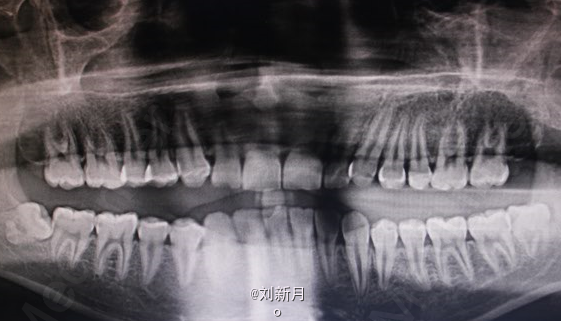

主诉:地包天求矫治 既往史:无矫治史,无牙科治疗史,无外伤史,无过敏史,无口腔不良习惯,无家族遗传史 口腔检查:恒牙列,A7-B7;C7-D8。牙齿排列整齐 尖牙磨牙III类关系,前牙反合 中线对正 面型为凹面型 关节无弹响无压痛

口腔检查 前牙反覆合,反覆盖 拍头颅侧位片,曲面断层片